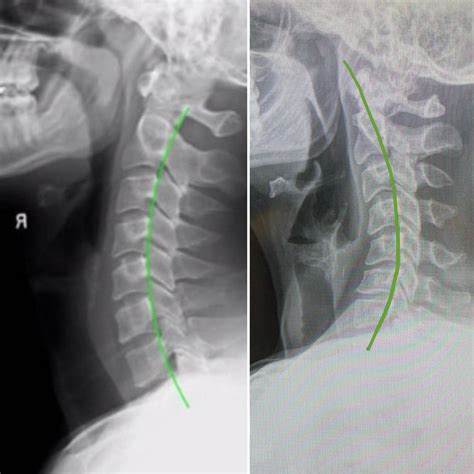

Interpreting a Normal Neck X Ray

Interpreting a Normal Neck X Ray involves examining the images for any abnormalities. Key structures to assess include:

• Vertebrae: The seven cervical vertebrae (C1-C7) should be clearly visible and aligned.

• Intervertebral Discs: The spaces between the vertebrae should be uniform and without narrowing.

• Joints: The facet joints should be well-defined and without signs of degeneration or inflammation.

• Soft Tissues: The soft tissues, including muscles and ligaments, should appear normal without any swelling or masses.

In a Normal Neck X Ray, the following features are typically observed:

Structure Normal Appearance

Vertebrae Well-defined, aligned, and without fractures or deformities.

Intervertebral Discs Uniform spaces between vertebrae, without narrowing or herniation.

Joints Smooth and well-defined, without signs of arthritis or inflammation.

Soft Tissues No swelling, masses, or other abnormalities.

• Kyphosis: A slight forward curvature of the cervical spine, which is normal in some individuals.